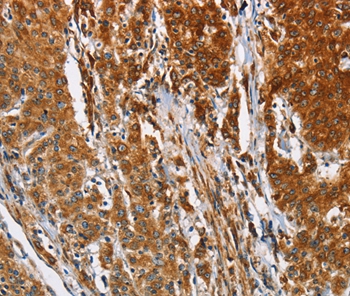

Immunohistochemical analysis of paraffin-embedded Human gastric cancer tissue using #36275 at dilution 1/30.